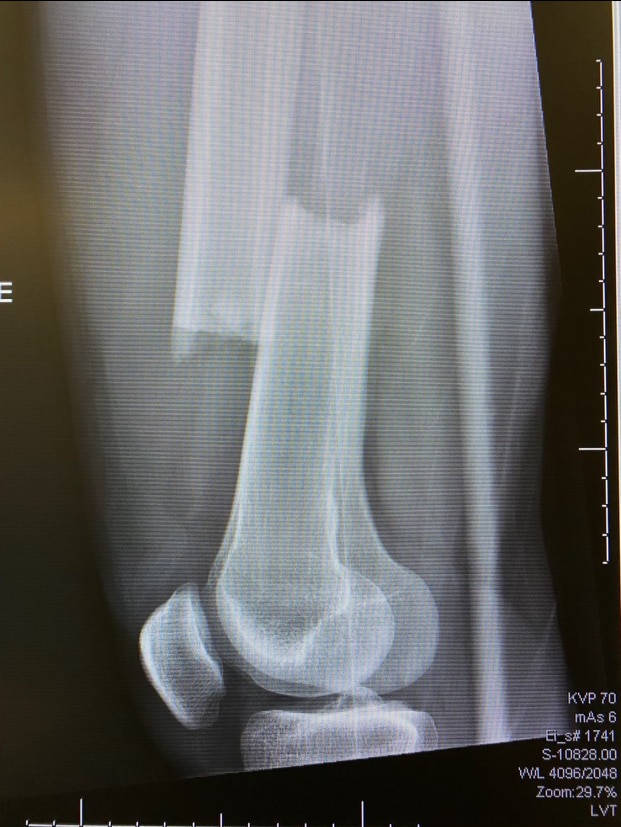

With a minute gone in the second period, Brodzinski skated the puck across the middle of the offensive zone. Eagles forward Trevor Kuntar hustled towards him from the opposite direction. The collision left Brodzinski on the ice, grabbing for his right leg. His femur was completely broken, a clean break.

Two hours later, he was in surgery at a local hospital getting a metal rod put in his leg.